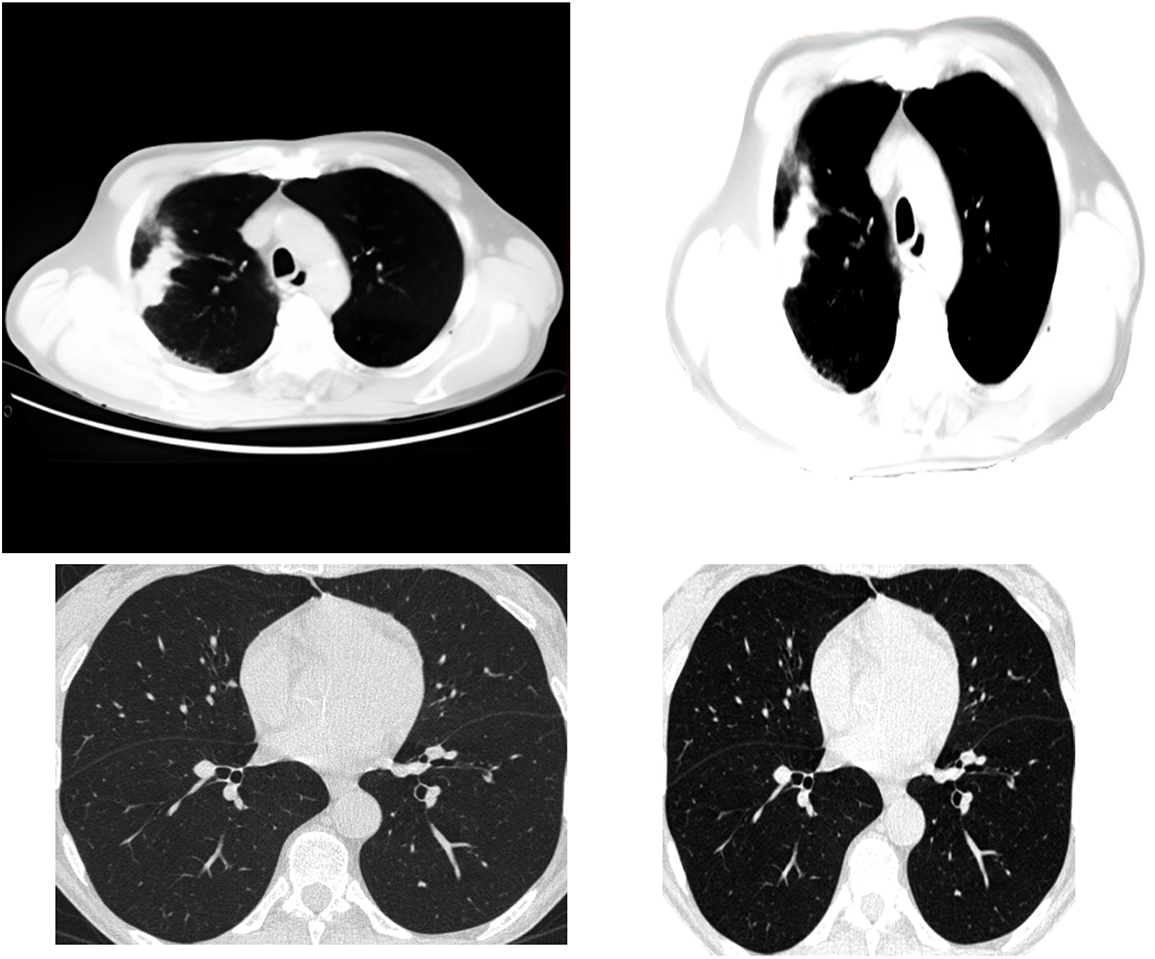

One of the methods of clustering is called central clustering. A duplicating technique repeatedly seeks locations as cluster centers, which have essentially the same mean positions for every cluster. Then it assigns each sampling dataset to a group that gives the least distance toward the center of each cluster for a certain number of sets. The centers of the groups are awarded points based on the degree to which they are similar, which ultimately leads to the formation of new clusters. This technique may be simplified to its most basic form by randomly selecting the cluster centers. Extracting features from the data using a first-order clustering technique is the procedure used for investigation. Fig. 2 presents the clustering approach that has been applied to it.

Figure 2: Applying the clustering algorithm to the image